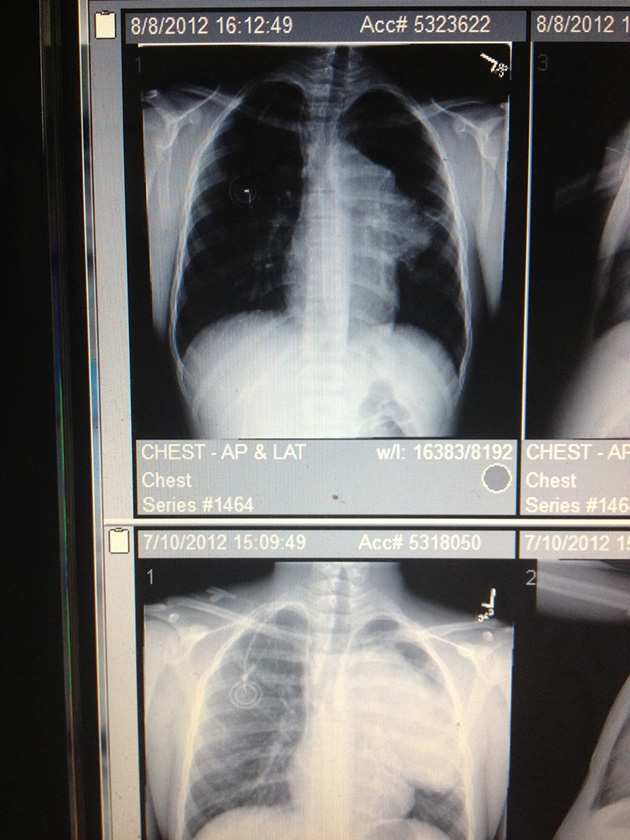

Comparisons of Edler's two MRIs.

​Above is a picture of two of Edler’s MRIs. The first one (bottom) shows an 11.5 centimeter long white mass (the tumor) taking over his right lung and pressing against his windpipe. The second one (top) shows a significantly smaller growth after his first 21-day cycle of chemotherapy.